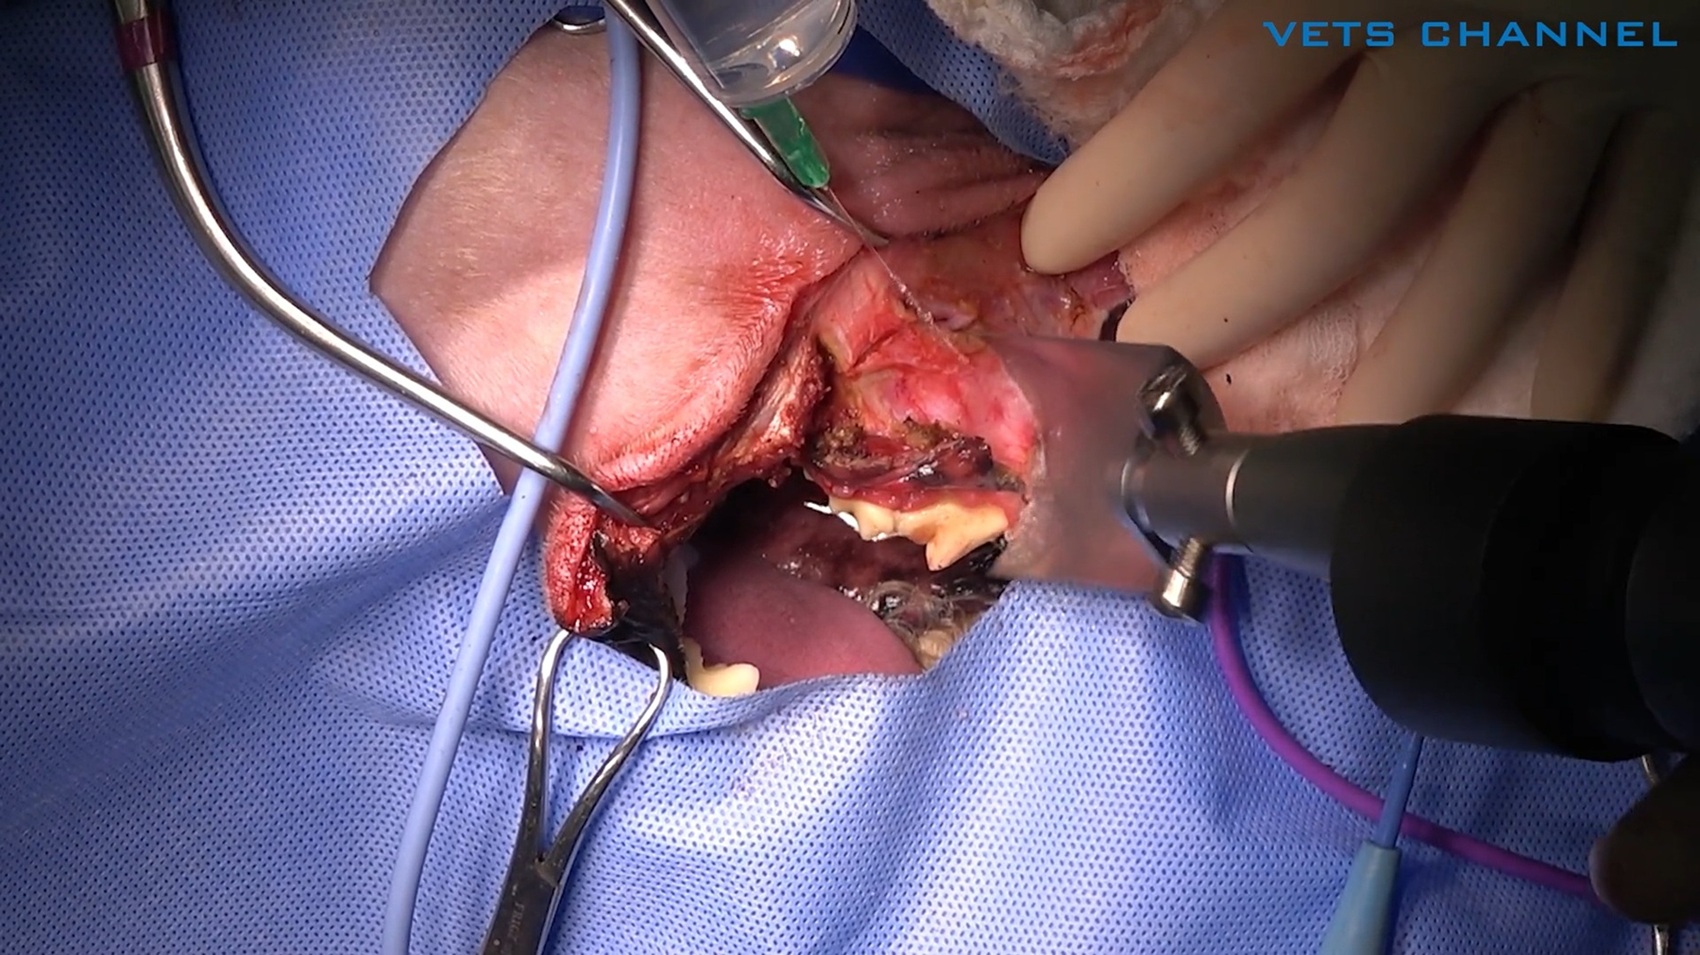

扁平上皮癌に対する上顎尾側切除術

小材 祐介先生 (伊勢崎動物医療センター)

27分

2025/11/07

扁平上皮癌に対する上顎尾側切除術

小材 祐介先生 (伊勢崎動物医療センター)

27分

2025/11/07